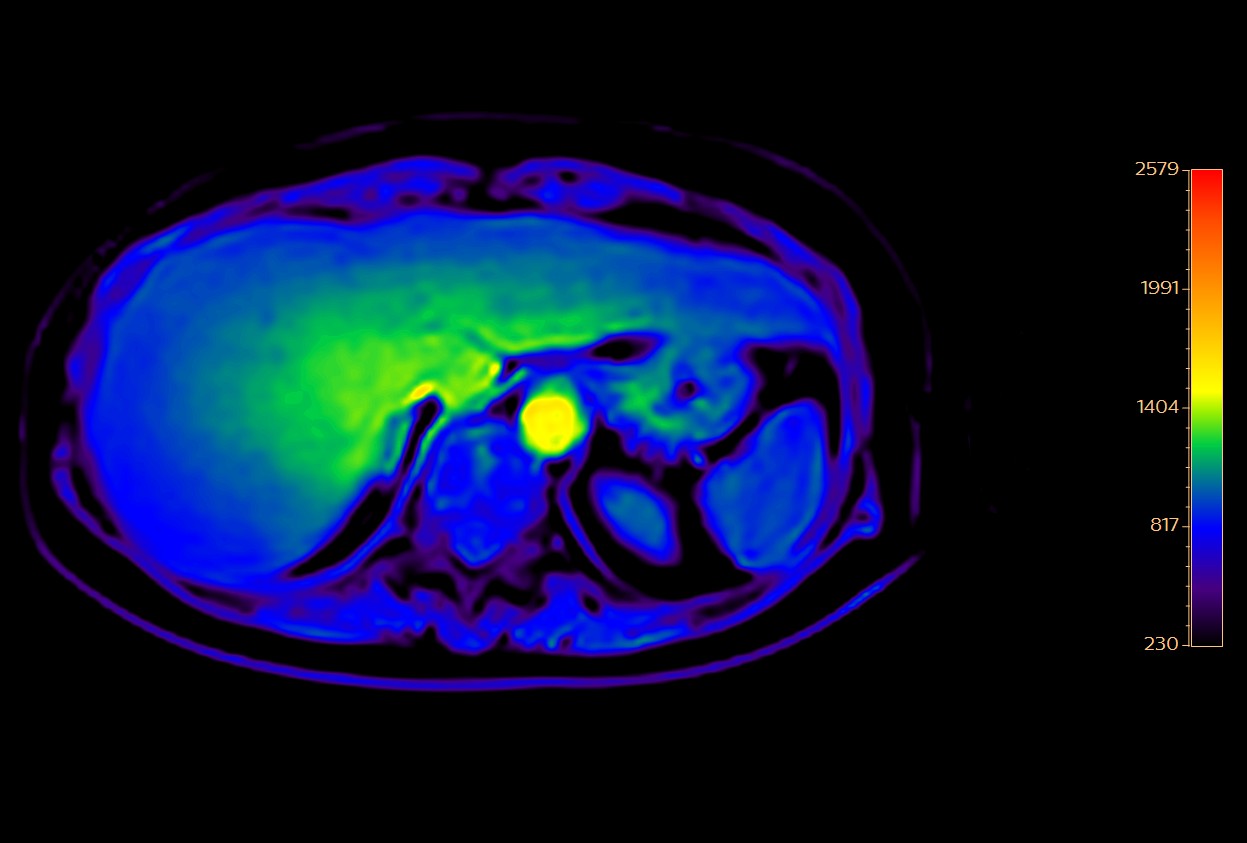

Liver metastasis with SmartSpeed Precise

Axial DWI ADC